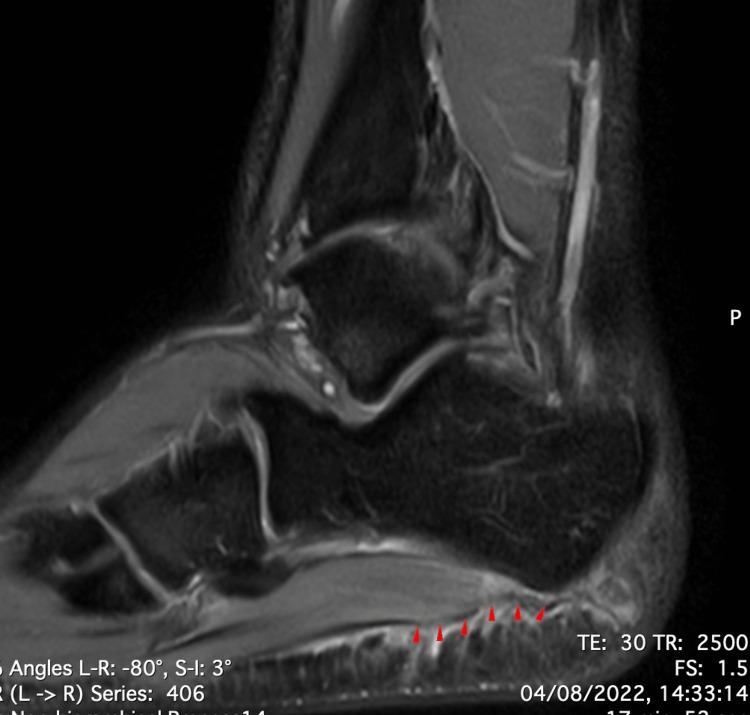

Acute rupture of the plantar fascia is a rare but potentially debilitating injury in athletes, particularly those involved in running and jumping sports. Early recognition and prompt treatment are crucial for a successful recovery and return to play. Conservative treatment, including rest, immobilization, and physical therapy, may be effective in most cases, while surgical intervention may be required in those that are nonresponsive to conservative treatment. We report a case of plantar fascia rupture in a 22-year-old male semi-professional football player who presented with sudden severe pain in the sole of his right foot during a match, followed by a popping sensation and inability to weight bear. The athlete was healthy and had no history of previous injury in the right foot. MRI confirmed a complete rupture of the plantar fascia. The player was treated conservatively and underwent a rehabilitation program. The player returned to full competition after nine weeks, with no limitations.

摘要

足底筋膜急性断裂在运动员中虽罕见但可能导致功能障碍,尤其是从事跑跳运动的运动员。早期识别和及时治疗对于成功康复和重返赛场至关重要。保守治疗,包括休息、固定和物理治疗,在大多数情况下可能有效,而对保守治疗无反应的患者可能需要手术干预。我们报告一例22岁男性半职业足球运动员足底筋膜破裂的病例,该运动员在比赛中突然感到右脚底剧痛,随后有爆裂感且无法负重。该运动员身体健康,右脚既往无受伤史。磁共振成像(MRI)证实足底筋膜完全断裂。该运动员接受了保守治疗并进行了康复计划。九周后该运动员恢复了全面比赛,没有任何限制。